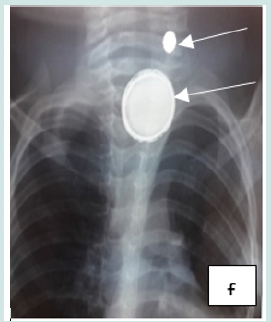

Cervico-thoracic X-ray performed in 211 cases (99%) showed opacity in 209 cases (99%). In one case, 2 circular opacities were observed, one of which had a double contour, indicating the ingestion of 2 foreign bodies (Figure 1: a, b, c, d, e, f). Foreign objects were a coin in 182 cases (85.4%), a shirt button in 4 cases (1.88%), a food in 7 cases (3.27%), and a flat battery in 3 cases (1.41%) (Table III). In 2 cases (1%) the EC was radiolucent.

Figure 6: f: circular esophageal CE of metallic tone, 2 opacities including one with a double contour (button batteries).